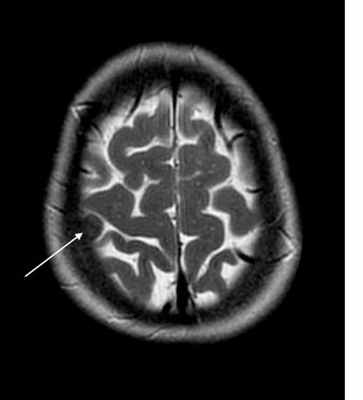

МРТ головного мозга. Т2-взвешенная аксиальная МРТ. Конвекситальная менингиома, цветовая обработка.

Менингиома – самая частая из неглиальных опухолей головного мозга. Она составляет 15-18% от всех опухолей головного мозга у взрослых. По классификации ВОЗ менингиомы могут быть трёх градаций, причём анапластические менингиомы (градация III) наблюдаются редко. Встречается менингиома чаще у женщин (Ж:М как 2:1) в возрасте 40-70 лет. Пятилетняя выживаемость в целом около 70%. 90% менингиом расположены супратенториально, причем половина из них находится по конвекситальной поверхности и связана с верхним сагиттальным синусом, как правило средней его третью. Реже встречаются другие локализации менингиомы – основание черепа, параселлярная область, сосудистое сплетение желудочка (обычно левого бокового), мосто-мозжечковый угол, орбита, большое затылочное отверстие, свободный край намёта мозжечка.

При МРТ головного мозга выявляется образование с широким основанием. Гиперостоз, часто видимый при КТ и на рентгенограммах, при МРТ головного мозга выглядит как утолщение внутренней костной пластинки свода черепа. Кальцинаты, обнаруживаемые при КТ в 20% наблюдений, при МРТ не видны. Опухоль при МРТ довольно однородная по структуре. Прорастание костей свода черепа видно отчетливо как участок повышенного сигнала на МРТ головного мозга любого типа в резко гипоинтенсивной кости. Сигнал от опухолевого узла на Т2-зависимых МРТ зависит от гистологического подтипа: относительно низкой интенсивности (между белым и серым веществом) при фибробластном и высокой при ангиобластном и синтициальном. Отек выражен в различной степени в каждом конкретном случае. Ряд МРТ признаков очень характерен для менингиомы: полоса ликвора между опухолью и тканью мозга, смещение окружающих сосудов. Они отражают неинвазивный характер роста. Смещенную и вовлеченную твердую мозговую оболочку иногда удается визуализировать при МРТ после введения гадолиния, особенно на корональных МРТ срезах. Усиление сигнала при МРТ с контрастированием от оболочки над опухолью с распространением в стороны (симптом “хвоста”) не абсолютно специфично и встречается при МРТ как при менингиоме, так и при лептоменингиальных метастазах. Однако при глиальных опухолях и невриноме при МРТ оно не описано. При обследовании пациентов методом МРТ в СПб с менингиомами серпа (фалькс-менингиомы) и намёта мозжечка рекомендуется делать МР-венографию для определения компрессии синуса и его проходимости. В наших центрах это обязательное исследование перед операцией. На открытом МРТ венография также легко выполнима. Не все центры МРТ СПб придерживаются этой методики.

МРТ головного мозга. Менингиома свода черепа (стрелка). Аксиальная Т2-взвешенная МРТ.